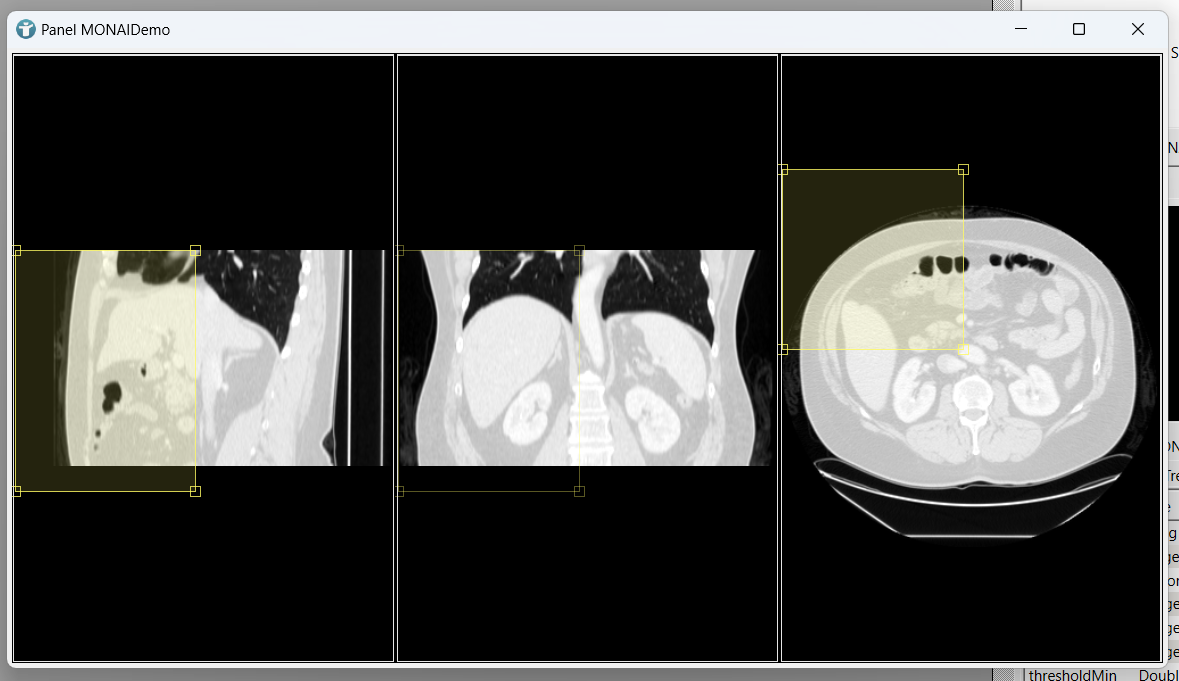

If you now open the panel of our MONAIDemo module, we can manually move the box in all three dimensions.

If you now load an image using the itkImageFileReader module, you can manually adapt your bounding box to include the spleen and start segmentation.